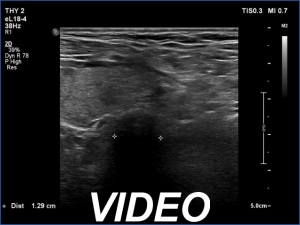

Ultrasonography. The right lobe was echonormal and intact. A large mass occupied almost the entire left lobe. On this side, normal thyroid tissue could only be identified in the dorsal part. The mass was composed of echonormal and hypoechoic areas, had macrocalcifications, irregular intranodular vascularity and proved to be very hard on elastography. There were multiple lymph nodes in III, IV and V left neck compartments. One of the nodes was in close proximity to the jugular vein and was suspicious of having broken into the vessel. The trachea was significantly narrowed at the lower level of the thyroid.

2. There are several remarkable findings in this case, e.g., the destruction of the left lobe by the tumor, the elastography pattern, the relation of the largest metastatic lymph node and the jugular vein, the ultrasound demonstration of the trachea' stricture.